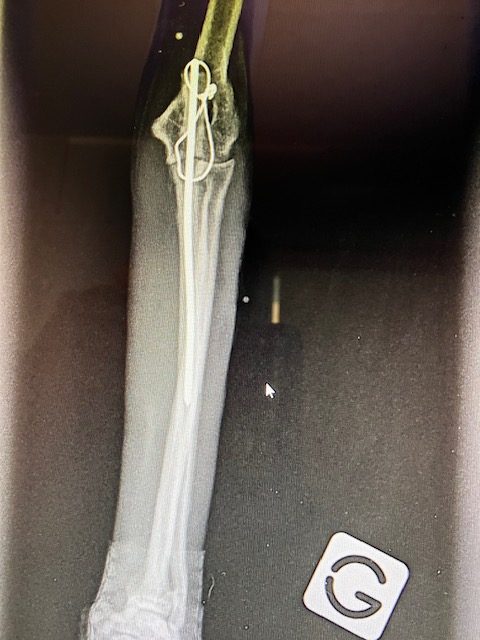

Un examen radiographique est réalisé sous légère sédation et après administration d’antalgique.

Dans notre cas, la Fracture – bien visible sur la radiographie de profil – est localisée sur l’Ulna, au niveau de l’articulation, dans la zone de l’échancrure sigmoïdienne. La Pointe du Coude – appelée l’Olécrane – est basculée en arrière. En effet sur son extrémité s’accrochent les tendons des puissants muscles triceps du bras, qui permettent le mouvent d’extension de ce dernier. Le triceps déplace donc en arrière et vers le haut l’olécrane fracturé. Cette fracture est simple, transverse, légèrement oblique. Le Radius est intact, en place. Dans ce type de fracture, le choc traumatique génère souvent une luxation associée du coude, et notamment un arrachement important et grave des ligaments du coude : on parle alors de Fracture de Monteggia. Dans notre cas la fracture est plus simple, les dégâts ne semblent toucher que l’échancrure sigmoïdienne ulnaire.